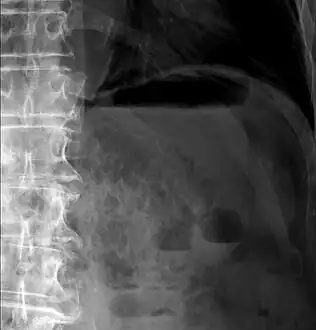

Pneumatosis intestinalis at computed tomography in intestinal ischemia. Lung window for better representation of the gas deposits in the intestinal walls. Coronal reconstruction.

Pneumatosis intestinalis in computed tomography with intestinal ischemia. Lung window for better representation of the gas deposits in the intestinal walls.- Upright AP radiograph showing gas in the wall of the small bowel in the left upper quadrant indicative of pneumatosis intestinalis.